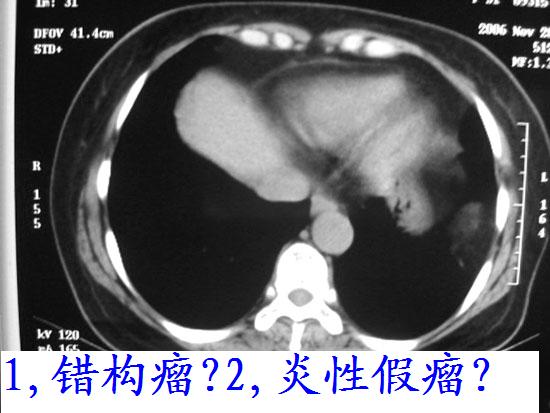

考虑错构瘤

ct图片少难度太大,考虑1、左侧包裹性胸腔积液  2、炎性假瘤

图片少、质量不佳,难度大,考虑错构瘤。

ct图片少难度太大,我考虑1、左侧包裹性胸腔积液  2、炎性假瘤